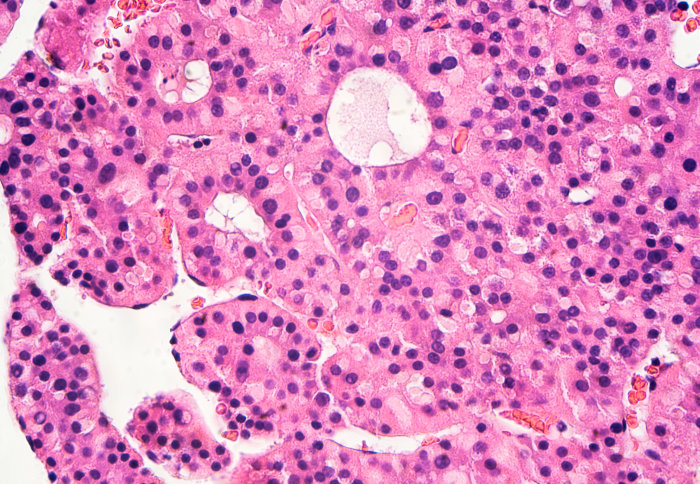

liver cancer

In this month’s podcast from the Institute of Global Health Innovation, we speak to Abellona U, Research Postgraduate from Department of Surgery & Cancer, Faculty of Medicine. She discusses how far we’ve come in cancer technologies, their translatability to lower and middle income countries and her research on hepatocellular carcinoma.